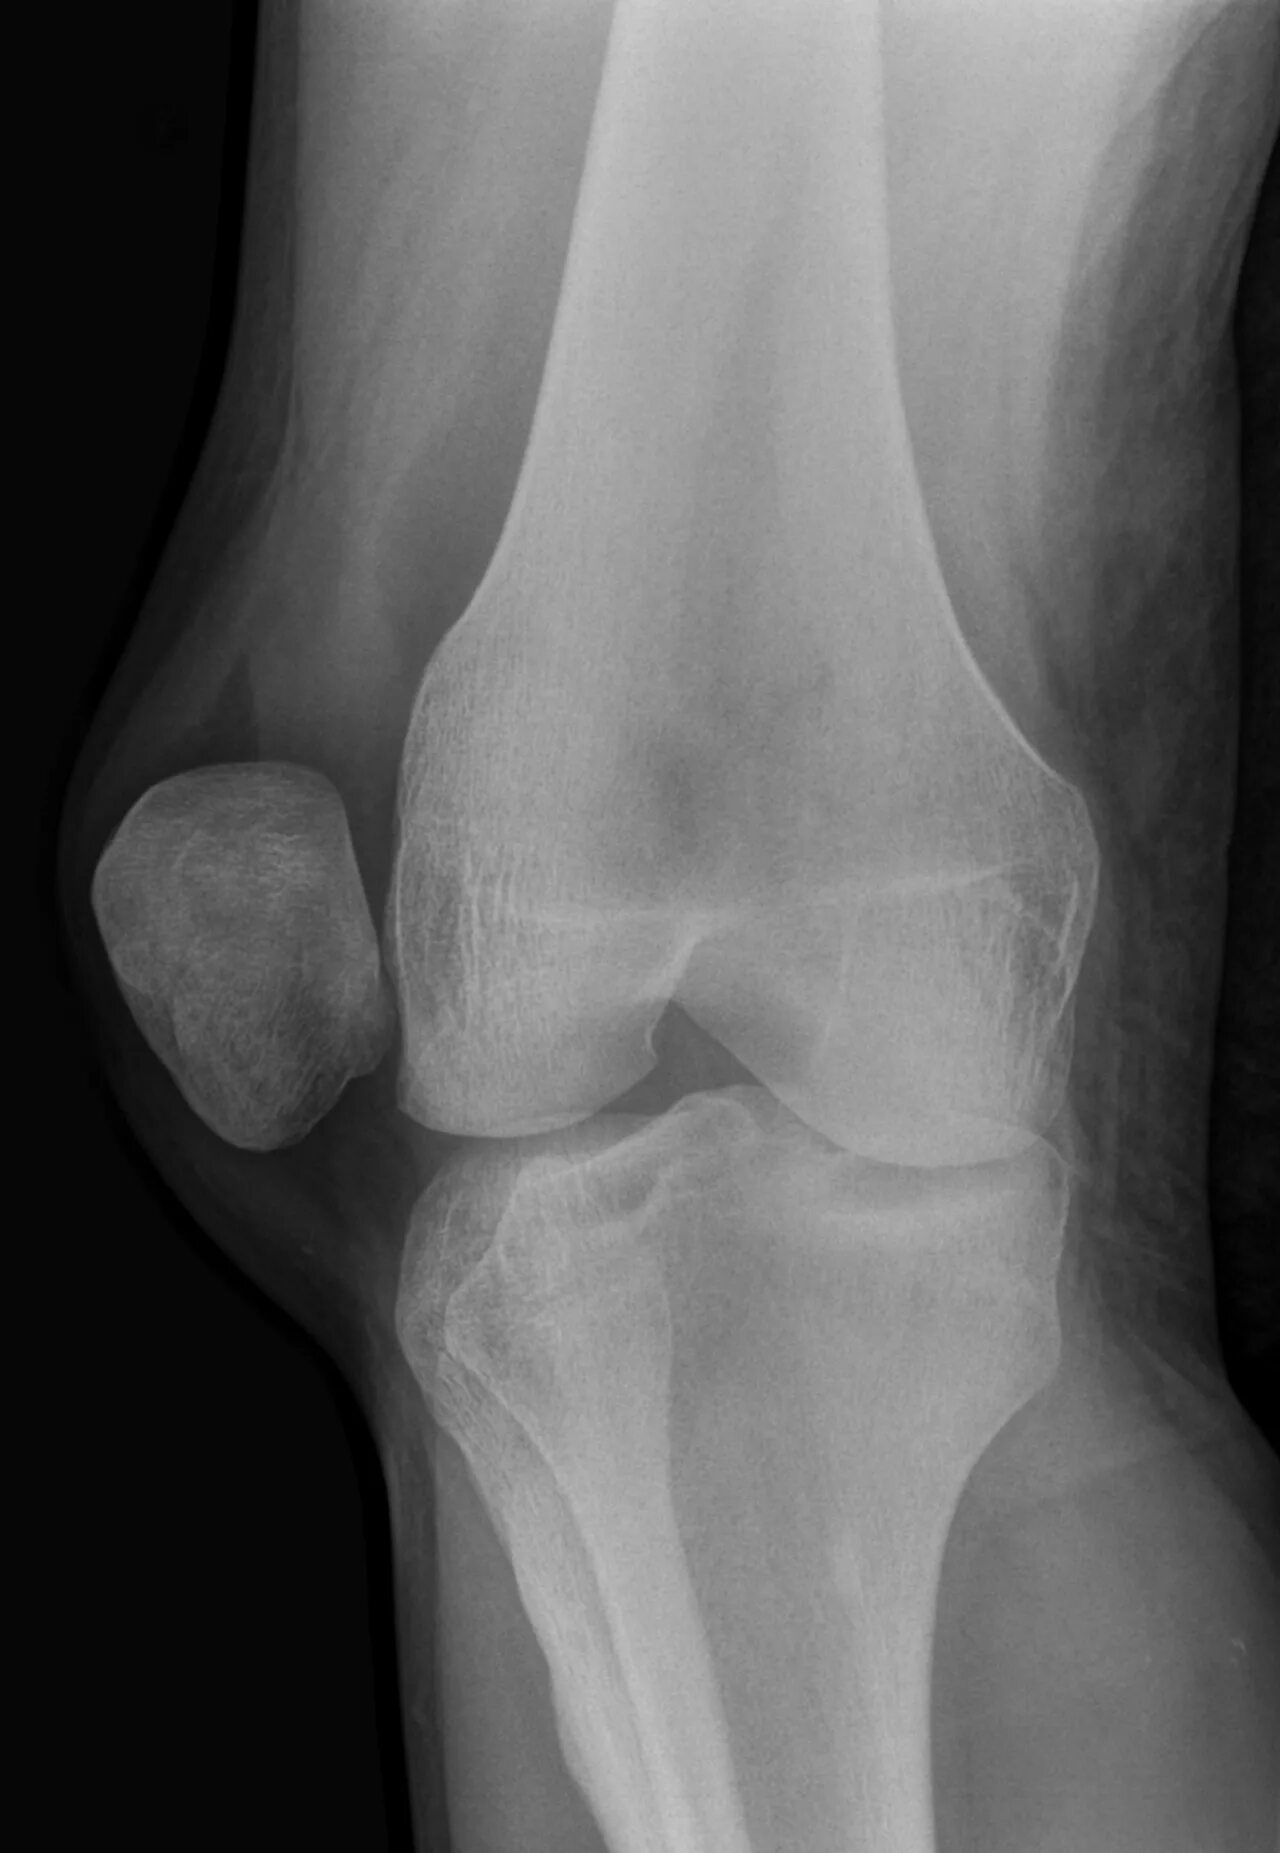

Как выглядит подвывих